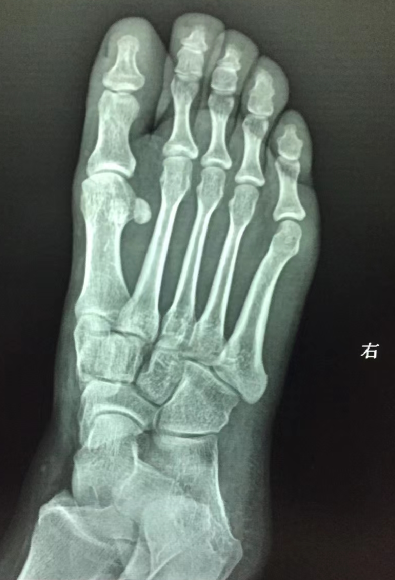

足正位看到内侧楔骨内侧见骨皮质断裂,横行线样透亮影.

右足第五趾骨基底部骨皮质断裂,可见线状透亮影,骨折断端未见明显错位